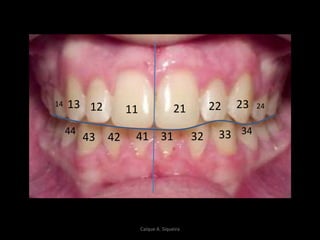

1112 21 22

314142 32

13 23 2414

343344

43